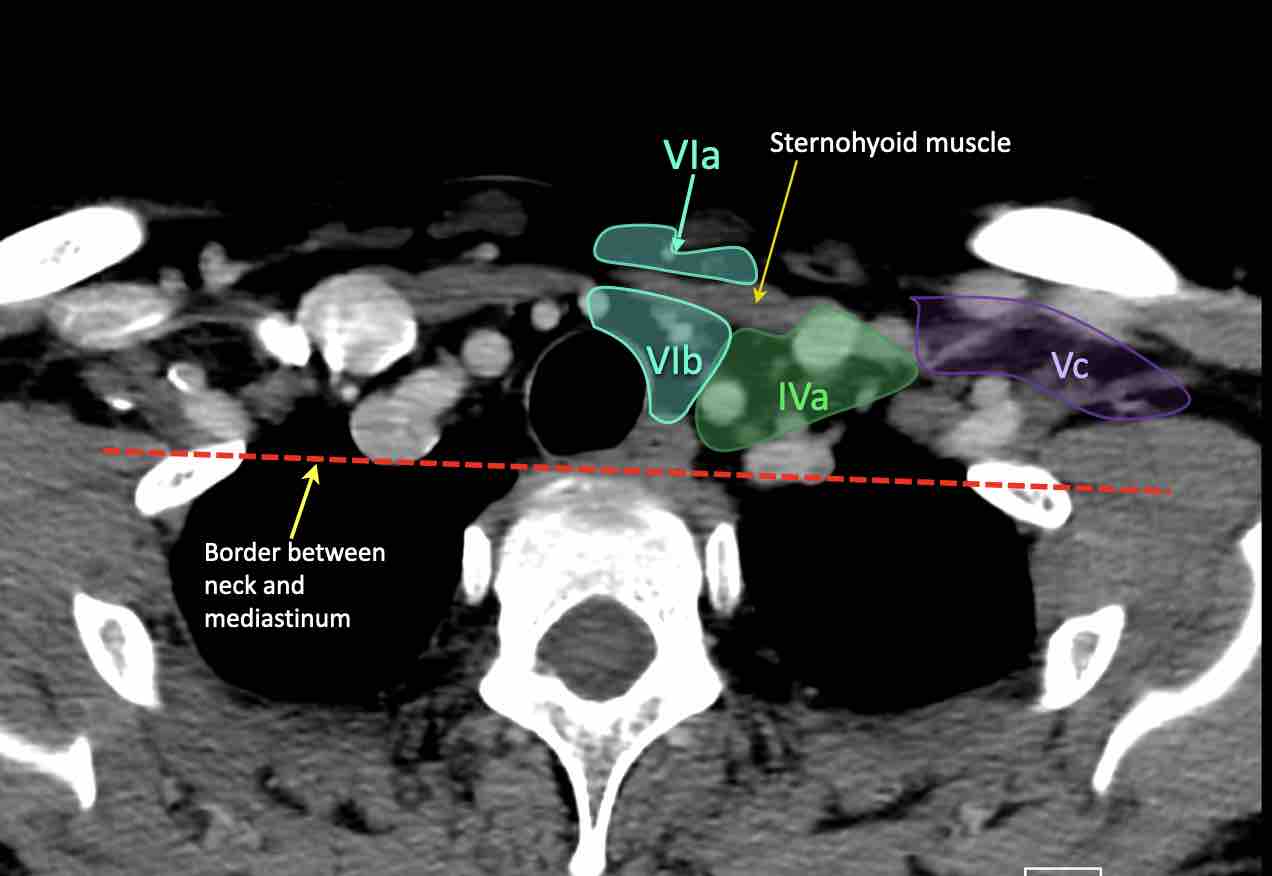

CT Scan Mặt Cắt Ngang (Axial CT)

Các lát cắt CT mặt phẳng ngang tương ứng với hình minh họa tổng quan.

Các lát cắt CT mặt phẳng ngang với hình ảnh chi tiết hơn.

Tầng Vc – Hố thượng đòn

Tầng này chứa các hạch thượng đòn bên nằm trong phần tiếp nối của các hạch tam giác cổ sau (tầng Va và Vb) từ các mạch máu cổ ngang xuống đến giới hạn được xác định tùy ý tại vị trí 2 cm phía trên cán ức.

Tầng này tương ứng một phần với vùng được gọi là hố thượng đòn.

Tầng Vc nhận các bạch mạch hướng tâm từ các hạch tam giác cổ sau (tầng Va và Vb) và thường liên quan hơn đến các khối u vòm hầu [1].

VI – Cổ trước

Tầng này chứa các hạch tĩnh mạch cảnh trước nông (tầng VIa) và các hạch sâu hơn bao gồm hạch trước thanh quản, trước khí quản, cạnh khí quản và hạch thần kinh thanh quản quặt ngược (tầng VIb).